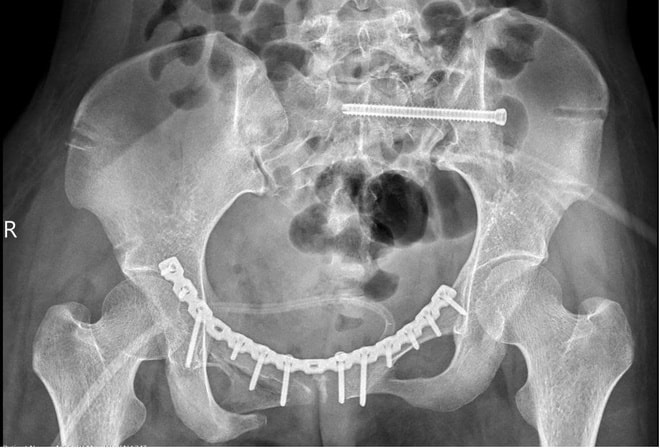

Sau 2 tuần điều trị tích cực, bệnh nhân được tháo cố định ngoài và phẫu thuật lần hai để nắn chỉnh lại các di lệch. Đến ngày 6/10, bệnh nhân có thể ngồi dậy và xuất viện về nhà.

Khung xương chậu bệnh nhân trước và sau phẫu thuật. Ảnh: BVCC.